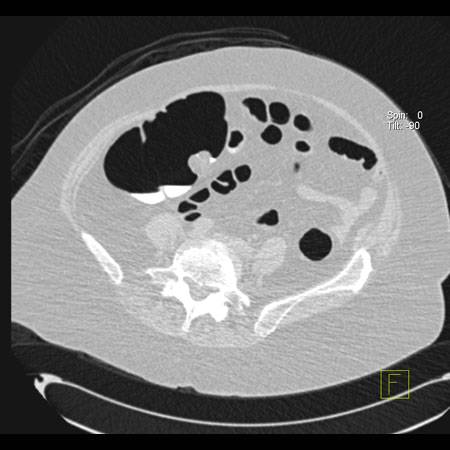

virtual colon: Mobile pills. Patient has Scleroderma. Notice the contour of the colon on the global images